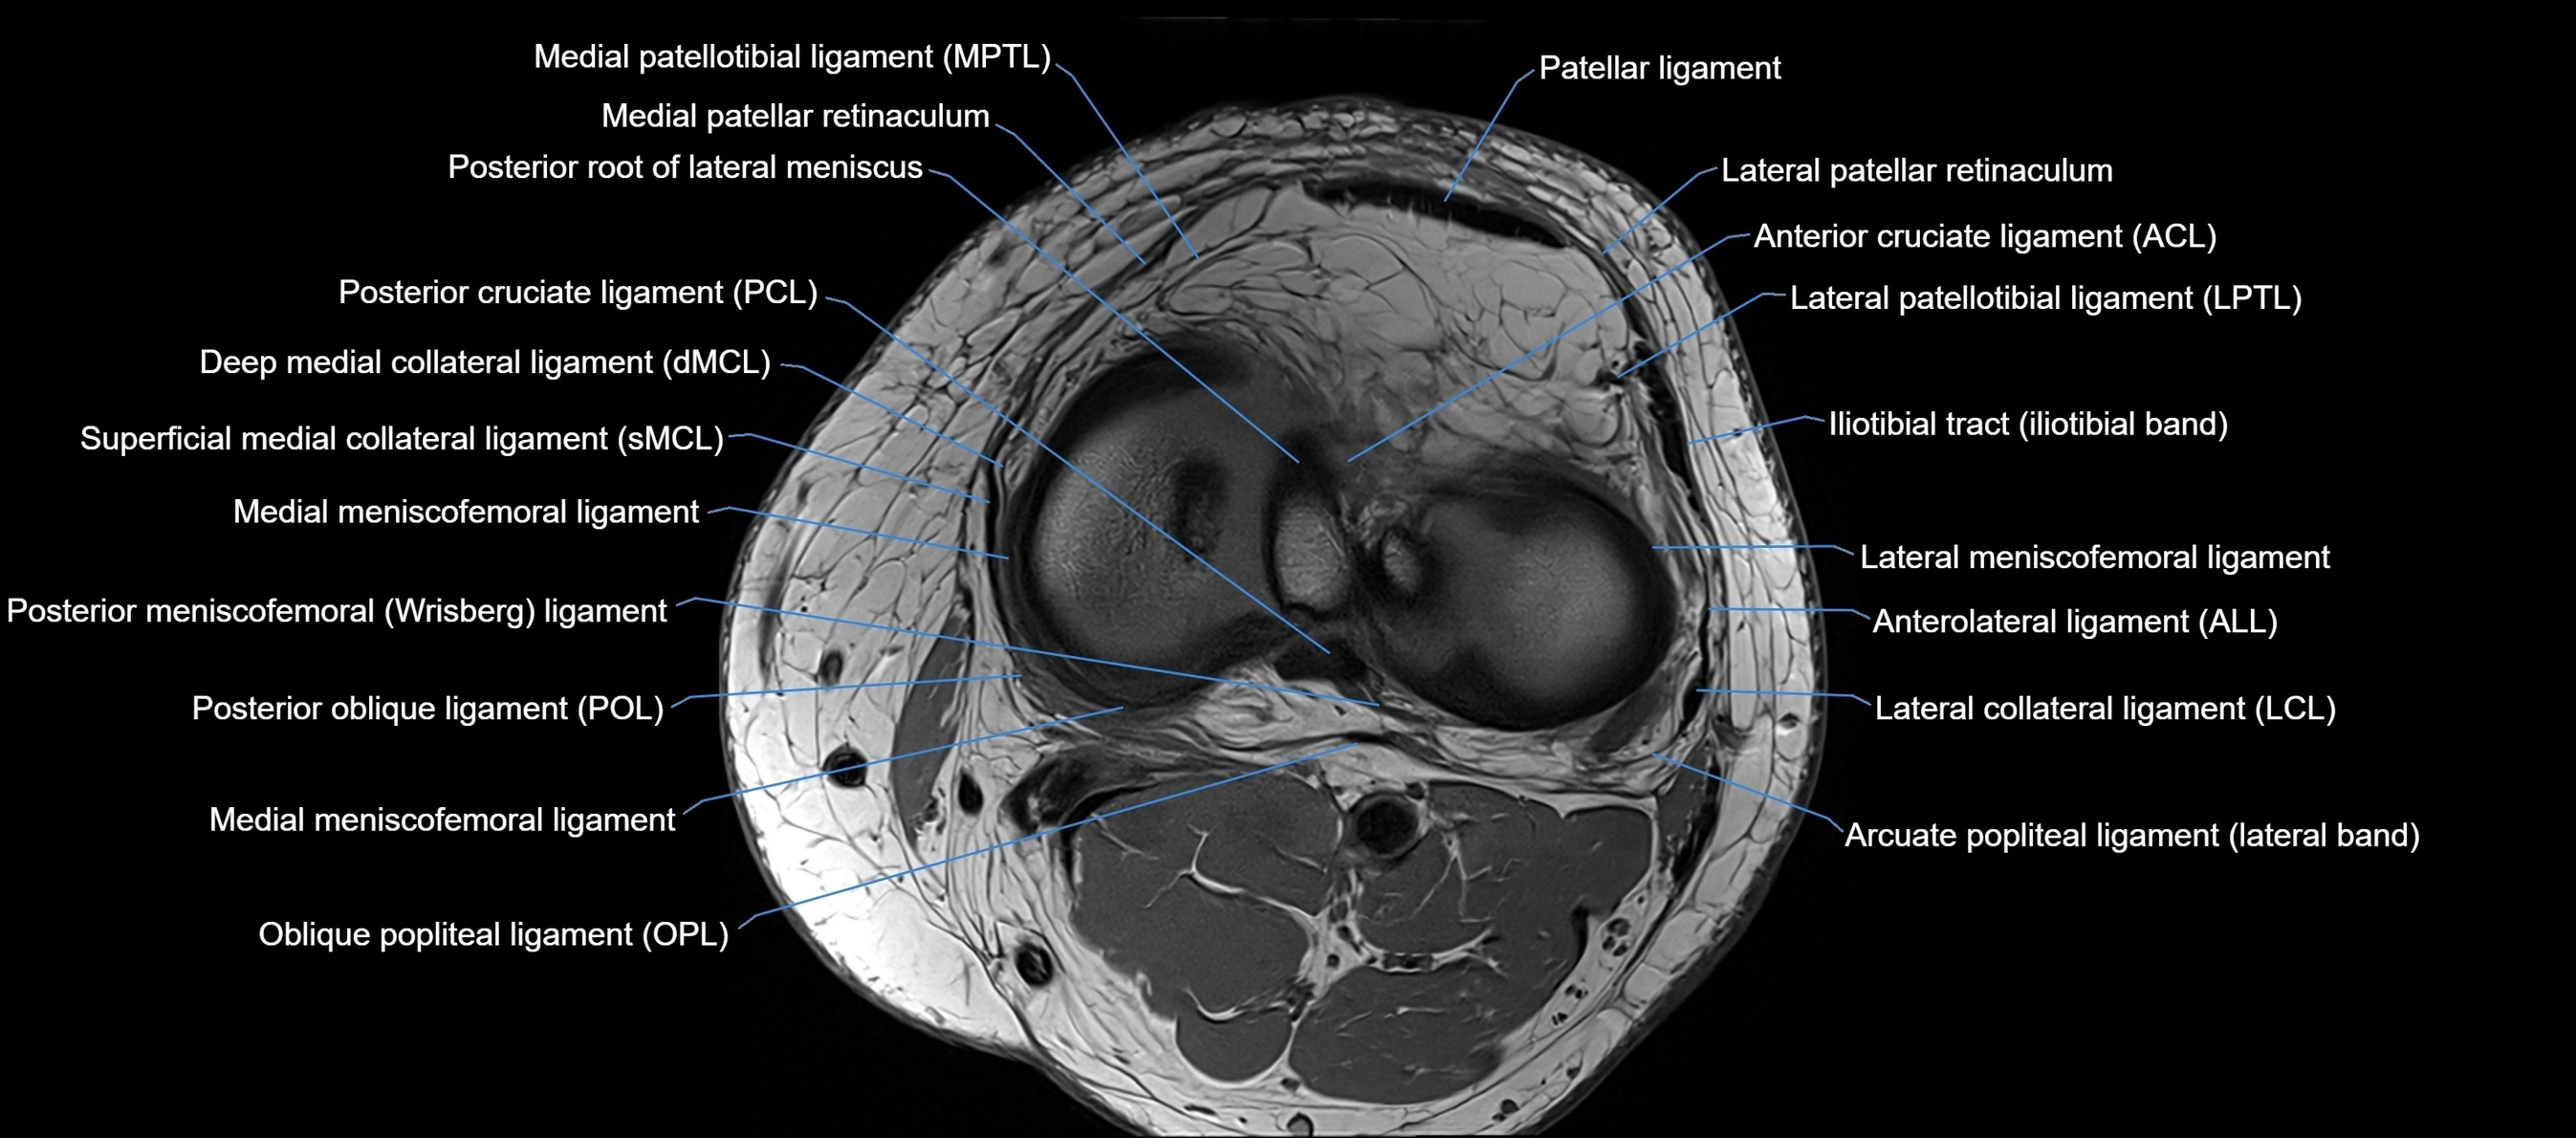

MRI images

image